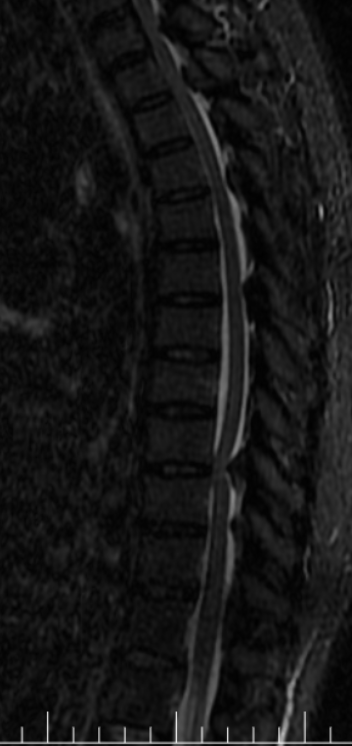

患者1+年前无明显诱因出现行走不稳症状,自诉有“踩棉感”,继而出行行走困难,近1+月明显加重,无法上下楼。对于一个居住在5楼(步梯)的患者来说,出门也变成了奢望。患者曾因为此症状反复就诊于省内外多家三甲医院,因体征不典型及相对复杂的既往史,曾被考虑为“糖尿病周围神经病变”、“焦虑症”等,长达1+年的治疗并没有使症状得到改善,反而逐渐加重,行走都只能靠助行器,甚至弯腰拾物简单的动作都不能执行,抱着尝试再一下的心态,患者就诊于我院,以椎管狭窄收入病房。入院早期因患者既往“焦虑症”的诊断,以及症状体征的不典型也给我科医务工作者在考虑诊断时造成了误导,经过反复积极查体考虑椎管狭窄,于是积极完善了脊柱的影像学检查,颈椎间盘、胸部及腰椎间盘CT:1、颈椎退行性变并颈椎椎管明显狭窄、颈2-3左侧椎间孔变窄;2、胸椎退行性变并胸1-7节段椎管轻度狭窄。胸腰椎MRI回示:1、颈椎退行性变并颈1-7水平后纵韧带增厚、钙化,继发椎管节段性狭窄。2、胸椎多段黄韧带增厚、钙化,继发相应椎管狭窄,脊髓节段变性(胸1-2及胸9-10水平)。结果出来后医生犯难了,问题找到的同时发现狭窄的地方及位置太多了,对于这种颈胸椎多处狭窄的病人想通过一个手术去解决几乎是不可能事情,针对此种情况,科内医师多次病例讨论,结合患者影像学检查、症状及体征,瞄准了T9-10平面的巨大黄韧带骨化。

此处黄韧带骨化严重,脊髓压迫严重,椎管狭窄处约只有4mm。考虑到手术难度较大,传统麻醉下手术瘫痪风险甚至可达20%以上,2022年6月24日科室内部邀请医务部参与最终讨论,报请重大手术,并决定使用局部麻醉与全凭静脉麻醉联合,保持术中唤醒随时检查下肢运动功能的麻醉方式,利用椎间孔镜可以直视的优点,行椎间孔镜下胸椎后路T9-T10椎板切除减压、黄韧带摘除、脊神经探查松解术。在2022年6月25日经过长达4小时20分钟的精细操作下最终将患者的压迫解除。几乎完整取出了巨大的骨化黄韧带。

术后积极控制血糖、血压,预防并发症,术后复查见: